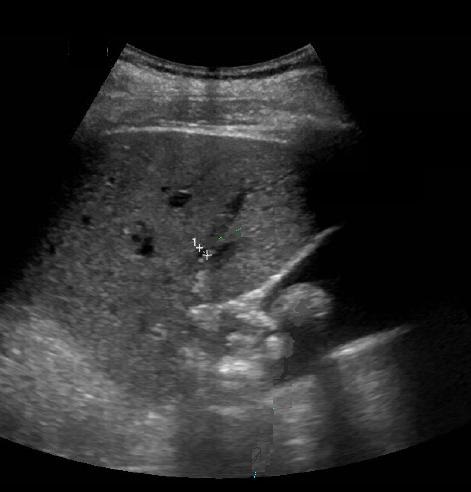

Echographie percutane

: Images echographiques du cholangite

infectueuse

aigue : Dilatation des voie biliaire intra et

extrahepatique , depasse 8mm avec voie

extrahepatique et 4mm des voies intrahepatique ,

Epaissisement de hypoattenuant de sa paroi . Image

de calcul canalicules et parfois de la

presence de pus intracanalaire .

Image

dilatation de voie biliaire intrahepatique.

Sa diametre de passe 6mm et image de calcul

vesiculaire se envoayait tres nette sur ce

coupe . Cholangite infectueuse |